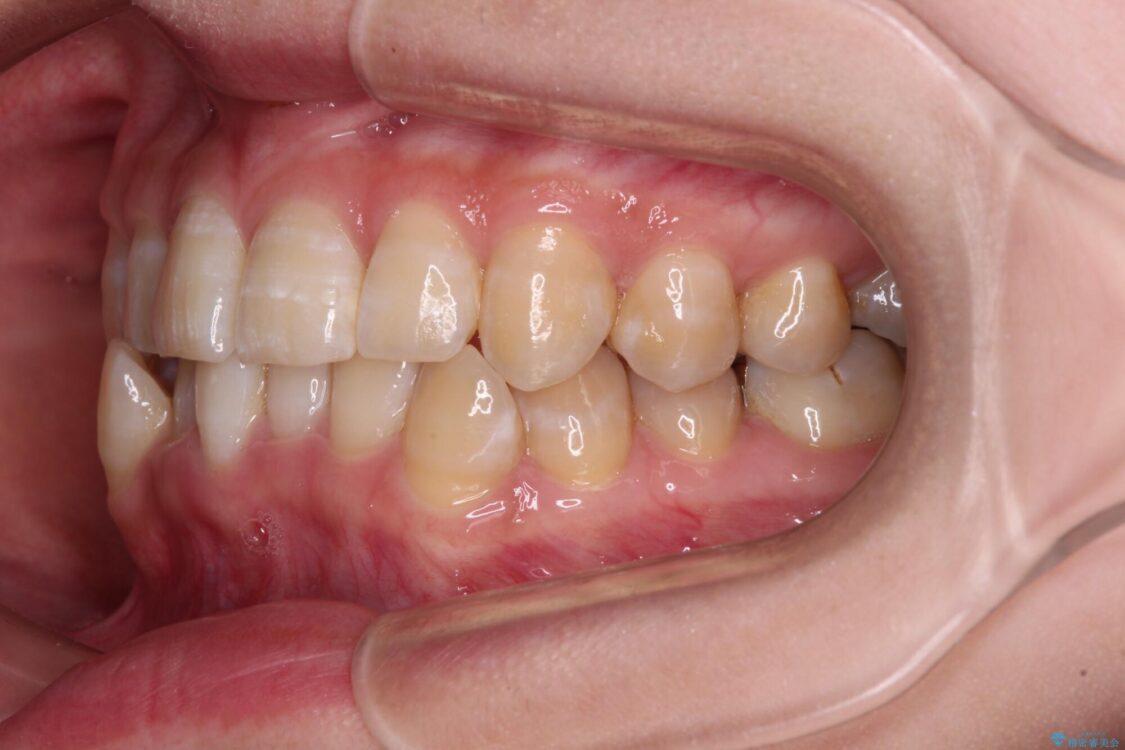

下顎の八重歯を気にして来院された患者様です。

下顎前歯にデコボコが集中していたため、顎間ゴムによる後方移動とIPR(歯と歯の間を削ること)により歯列を整えることとしました。

治療前、下顎前歯のデコボコが集中しており、奥歯の咬み合わせは、上顎に対して下顎が前方位にある状態でした。下顎の歯列を後方へ移動させる治療はインビザラインの得意とするところですので、1年程度で無事に治療を終えることができました。

治療前

• 【モニター】下顎前歯のデコボコをインビザラインできれいに 治療前画像